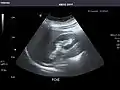

Spleen

Spleen: Normal in size.